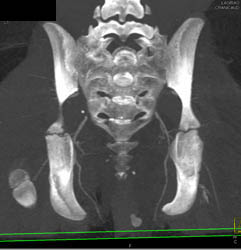

Diagnosis

Open Reduction Internal Fixation (ORIF) of Tibial Fracture